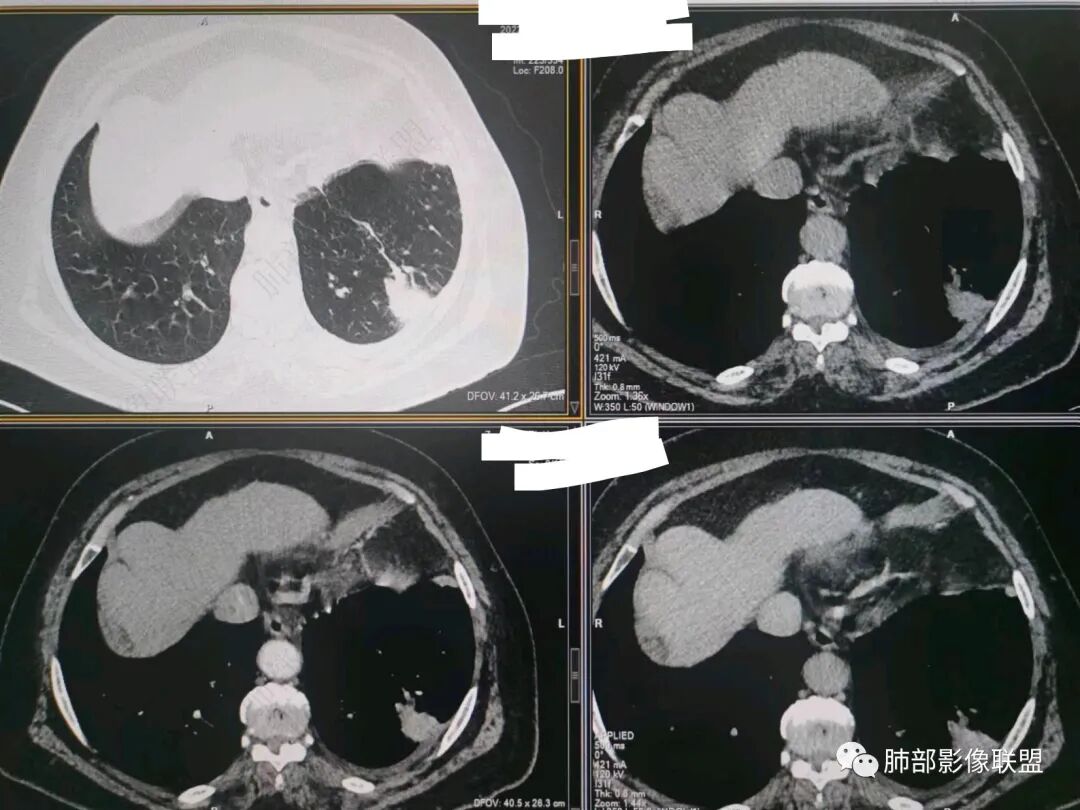

秦化君:左肺下叶外基底段胸膜下软组织密度结节性,边缘毛糙与血管相连,密度不均,增强后病灶内边界不清低密度区,胸膜栽桩,少量胸腔积液。考虑恶性病变,腺癌可能。真菌待排。

谢加平:老年女性,慢性咳嗽,咳白痰史,左肺下叶后基底段胸膜下肿块,类圆形,边界清膨隆,密度不均匀,低强化及小灶性坏死,坏死轮廊不清,胸膜下栽赃明显,左侧胸腔少量积液,向胸壁肌侵犯,另肿块近心侧见支指套征,粘液低密度,支持恶性,粘液腺Ca,经皮肺穿刺活检明确诊断。

361度:老年女性,发热,胸部CT示左下肺胸膜下结节影,血管集束,毛棘,密度不均,胸膜栽赃,少量胸腔积液,不均匀强化,坏死边界不清,肿标轻微升高,考虑恶性,鳞癌合并感染。

红星:老年女性患者。胸膜下结节病变,明显的膨胀,并局部侵犯胸膜,增强明显的强化。病灶周围带有局灶的渗出性改变以及条索上的影。考虑腺癌的可能性大,鉴别结核肉芽肿性病变。

宇宙:左肺下叶胸膜下球形肿块,边界尚清,局部平直,局部膨隆,内侧缘长索条,胸膜栽赃,轻度不均匀强化,其内坏死边界欠清,左侧胸水,考虑腺癌,鉴别放线菌。

袁媛:左肺下叶胸膜下球形肿块,宽基底连于胸膜下,胸膜栽赃,边缘膨隆,有血管供应,增强有强化,考虑腺癌。

songml:老年女性,反复咳嗽咳痰胸闷4年,加重伴发热一周。左肺下叶后基底段胸膜下肿块影,密度较均匀,边缘较清,侵及胸膜下脂肪间隙。考虑恶性病变,腺癌可能,鉴别真菌感染。

人生海海:左肺下叶不规则形软组织密度影,膨隆生长,边缘清楚,分叶,棘突征,支气管截断,血管纠集,病灶轻度强化、内多发坏死,左侧少量胸腔积液,考虑粘液腺癌,鉴别肺脓肿。

位移:老年女性,左肺下叶肺胸膜下团块影,边界清、毛糙,膨隆,内密度不均,不均匀强化,内见坏死,胸膜栽赃,胸腔少量积液,首先考虑恶性肿瘤,低分化腺癌,鉴别小细胞癌,炎性假瘤。

放射线:左肺下叶后基底段胸膜下肿块,边缘膨隆,密度不均匀,内见低密度坏死,胸膜栽赃,左侧胸腔少量积液,考虑恶性,腺癌?鉴别放线菌,OP伴脓肿。

南边:今天的病例肺内部分基本都是炎性特点,问题就在于胸膜。

南边:看肺内病灶与胸膜分界清,增强后强化不一致,需要综合分析。